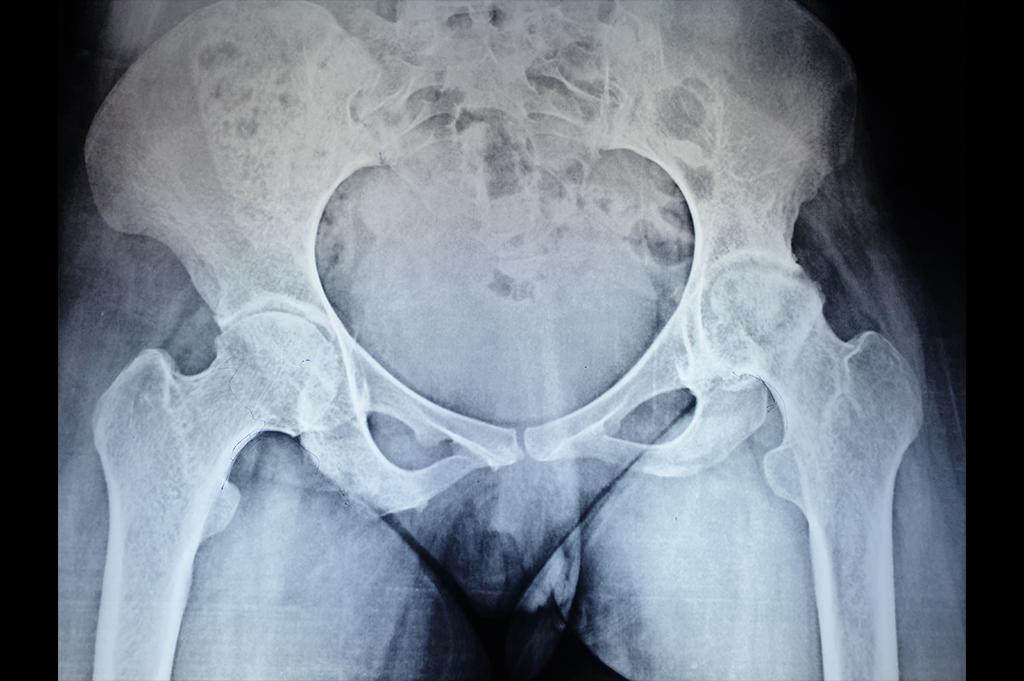

Neck Femur Fracture

Total Hip Replacement - THR